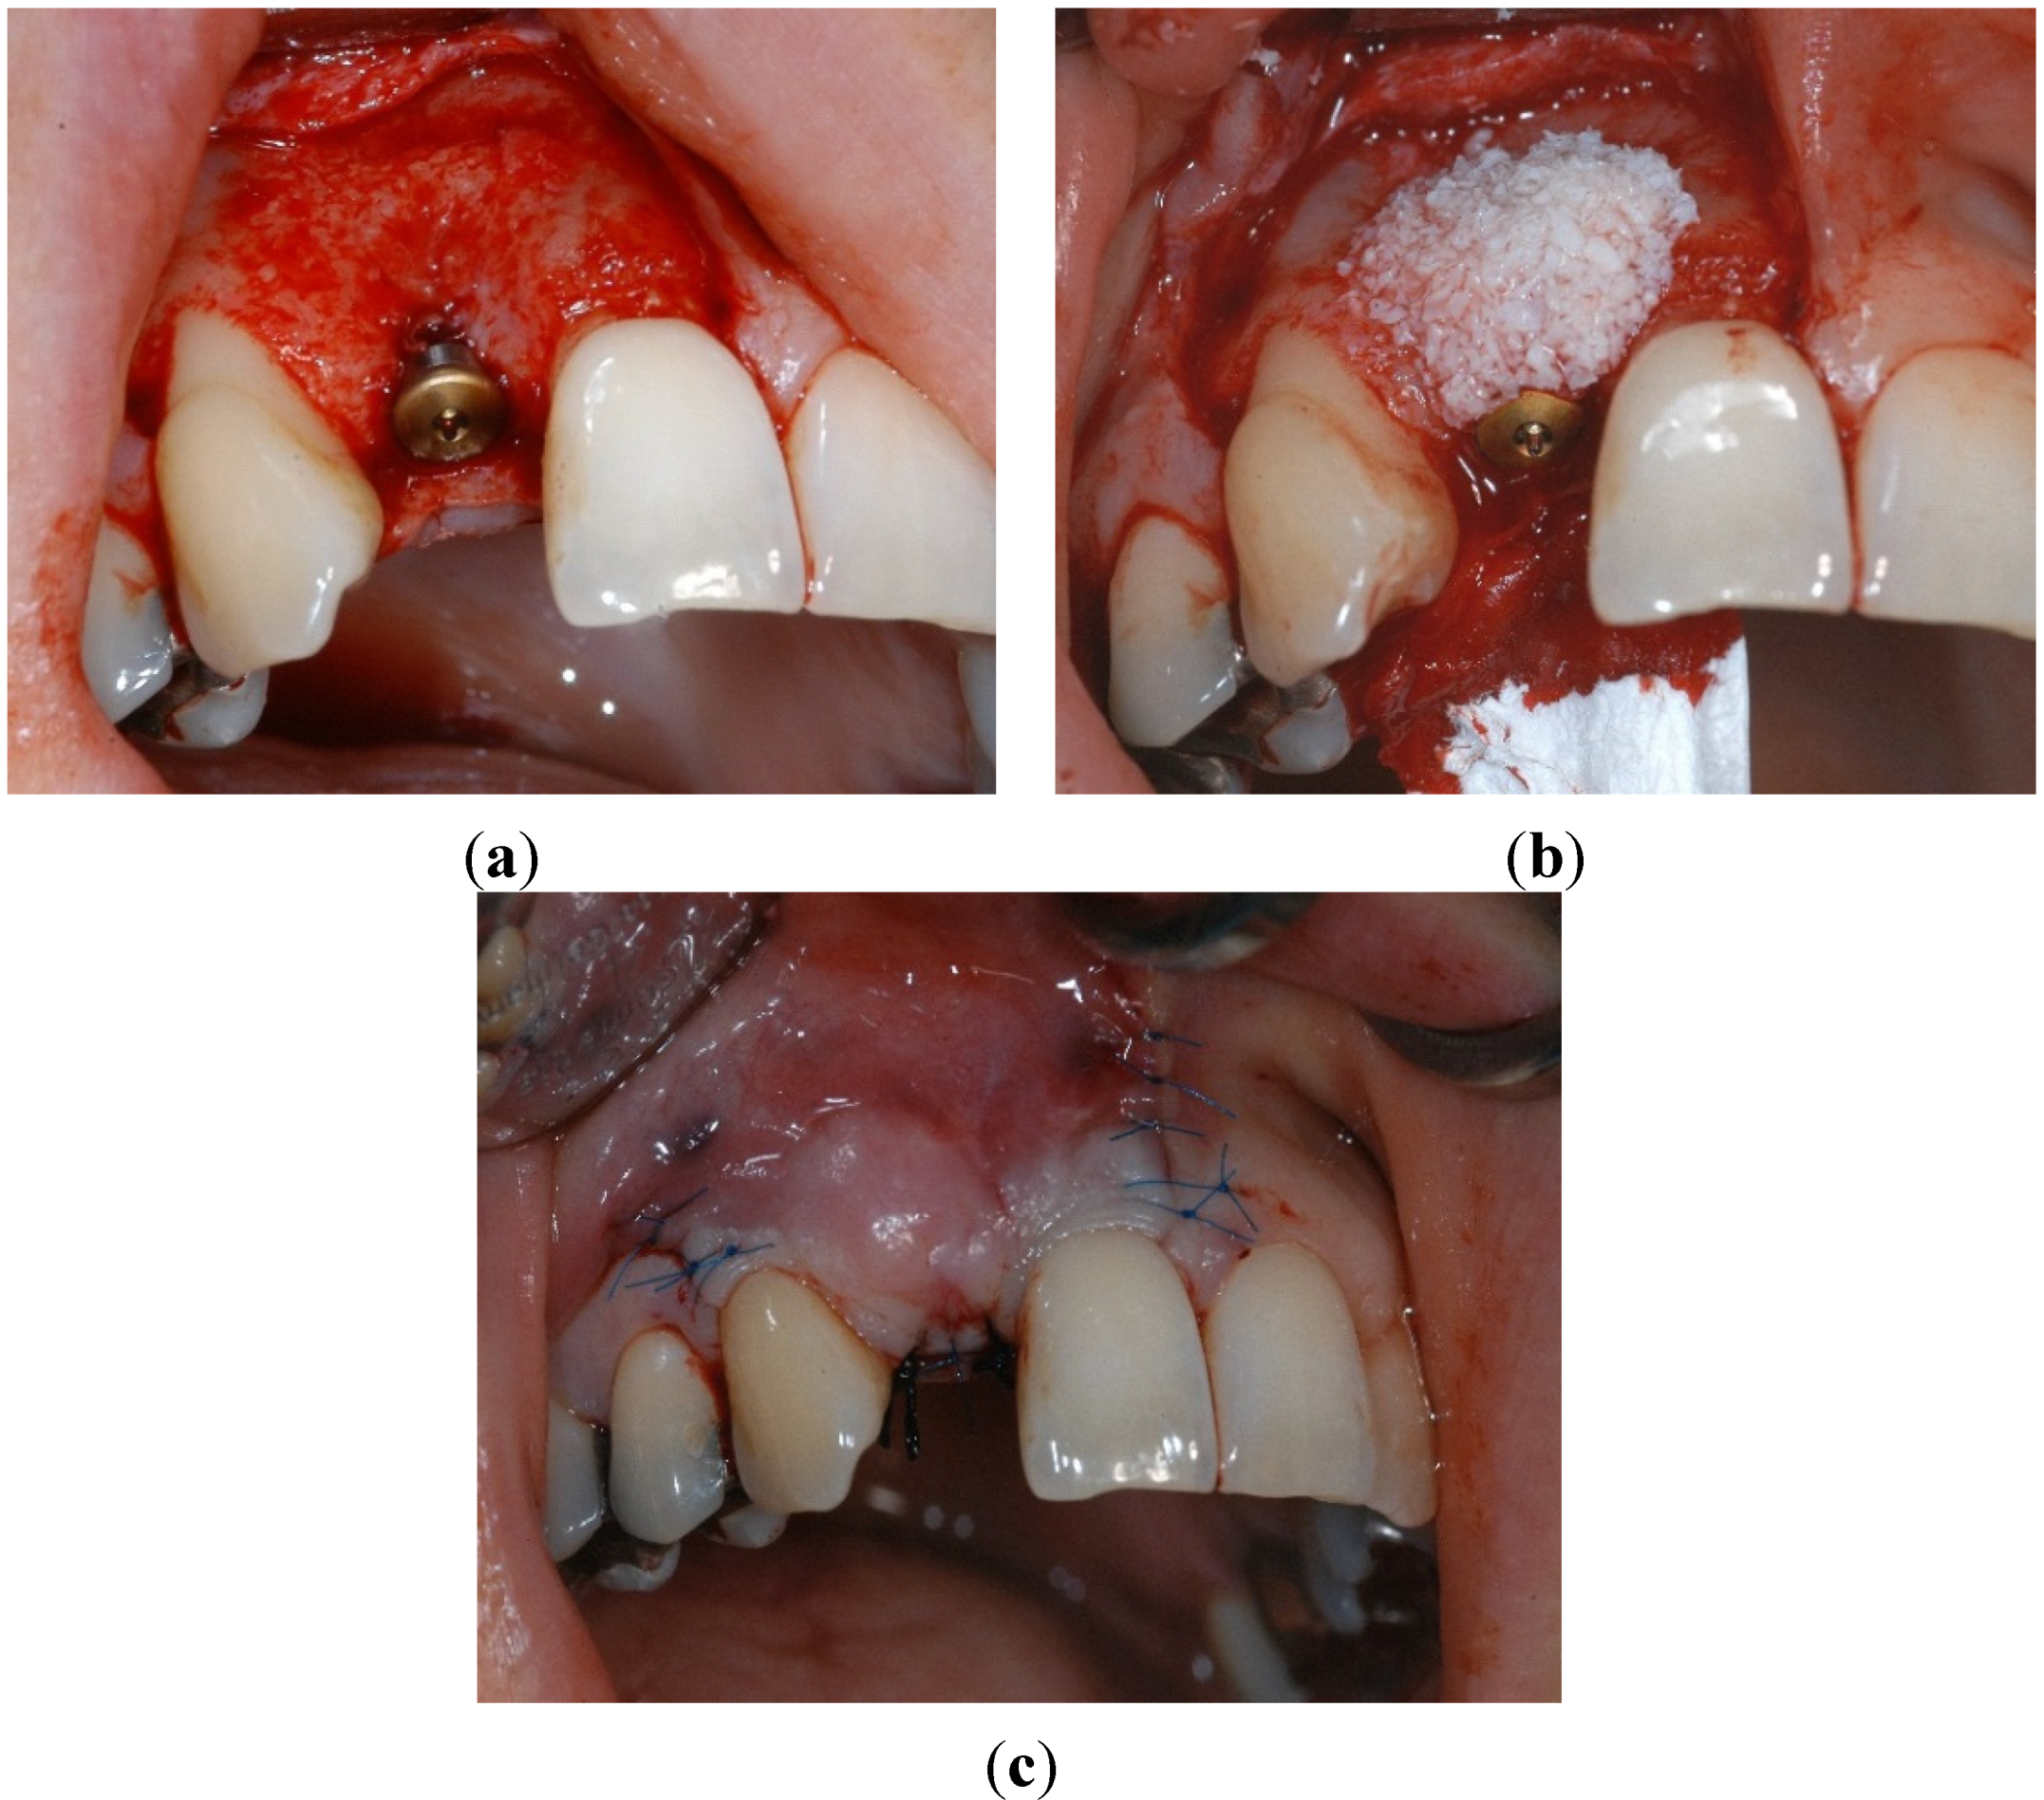

2.2. Materials and Methods

4.2. Surgical Characteristics